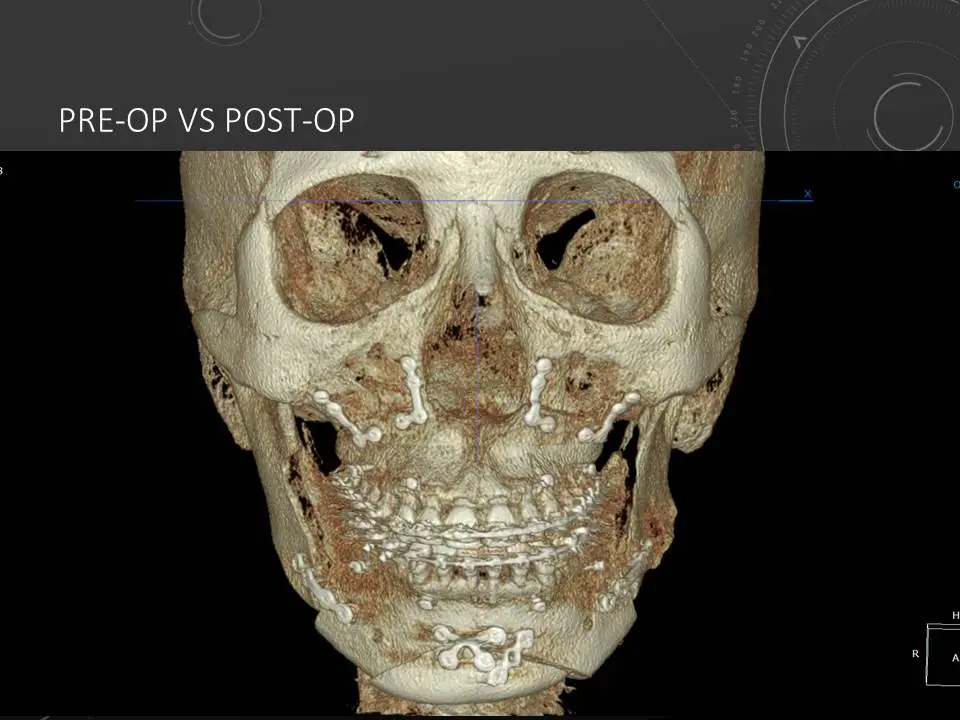

수술이 끝나고 나면 수술 후의 3D CT를 촬영하여 수술 전 후의 3D CT를 겹쳐보아 수술이 계획대로 되었는지를 확인할 수 있습니다.

슬라이드122.JPG

슬라이드123.JPG

양악수술 전 CT 사진(좌), 양악수술 후 CT 사진 (우)

화면의 좌측에 보이듯이, 수술 전에는 턱이 왼쪽으로 많이 돌아가 있었으나

화면의 우측에서 보이듯이, 양악수술을 통해서 대칭의 위치로 고쳐지게 되었습니다.